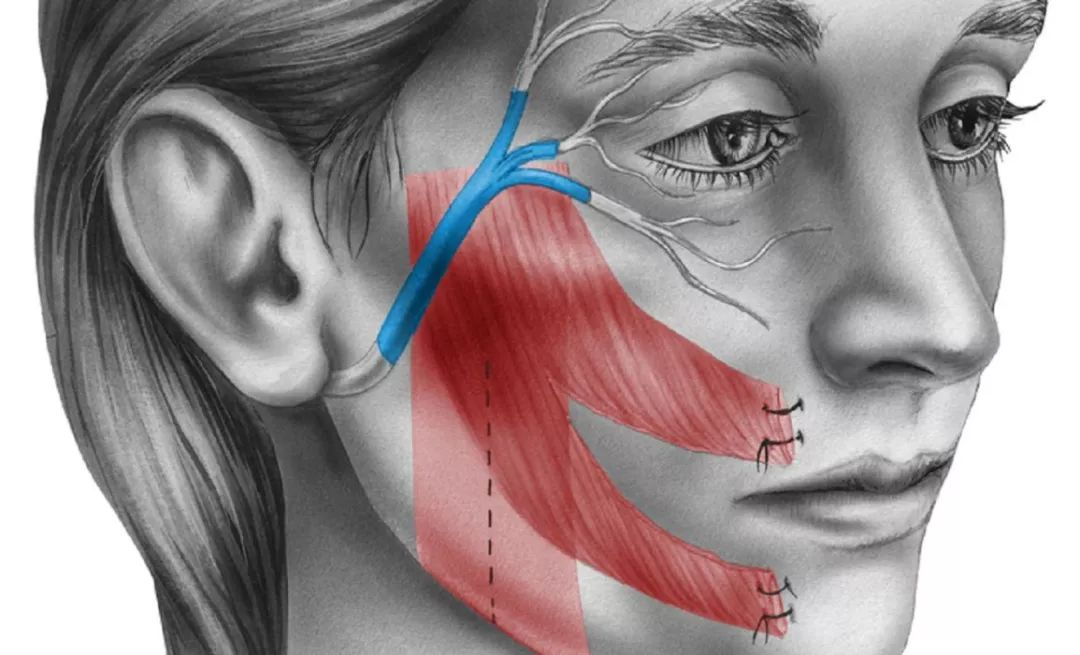

原来在治疗水痘的过程中,人体免疫系统确实把体内大多数的VZV病毒消灭掉。但仍会残留一些不能被血清中的抗体完全中和的VZV病毒。这些病毒发挥着自己天然亲近神经的特性,顺着皮肤的上皮感觉神经末梢不断逃离免疫大军攻击。最后,它们躲进了脊髓后根神经节的神经元或是颅神经的感觉神经节里,并在长期定居了下来。

脊髓后根神经节

要知道,这两大类神经节恰好是主管感觉的神经的汇聚地。从这里发出的感觉神经遍布于全身皮肤,会让人感觉到痛、冷、热等。可想而知,有朝一日当它们重新爆发时会有多痛苦。

与当初水痘痒得令人抓狂不同,带状疱疹是从神经发出的剧痛,分分钟让人痛不欲生。当然,这疼痛也是沿着那根受累的神经所支配的区域分布的。一些人带状疱疹只发在肋间神经的背后那段,就只有背后痛;另一些人发在面神经上,就半边脸痛。